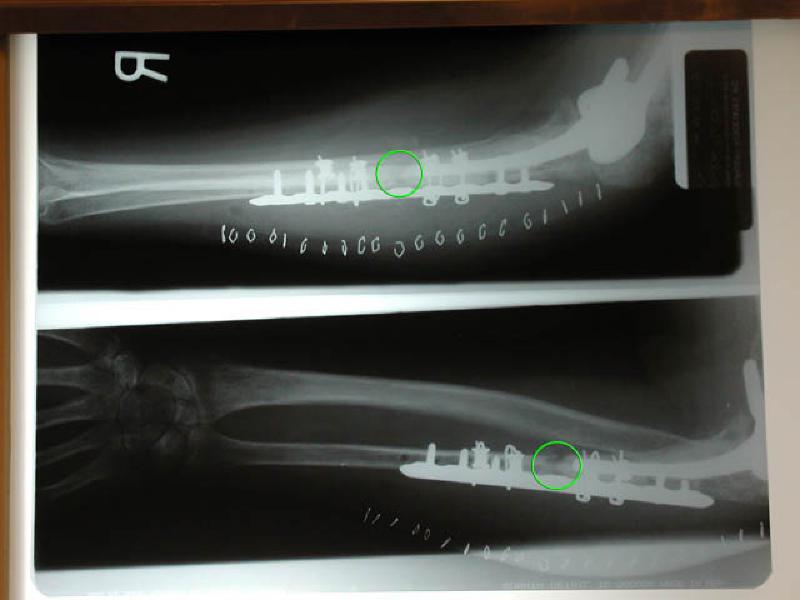

Marla's X-Rays show the repairs that Dr. Sachar performed on Marla's ulnar bone during her surgery on 12/8/2004. The green circles show where her ulna is broken. Dr. Sachar stabilized the bone by embedding a new plate, performing a bone graft in in the break, and utilizing a cadaverous fibula to provide support.